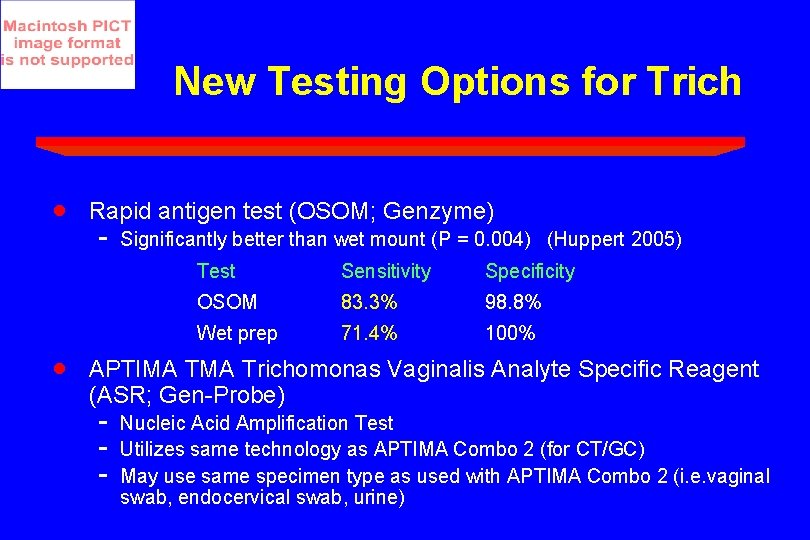

New Testing Options for Trich · · Rapid antigen test (OSOM; Genzyme) - Significantly better than wet mount (P = 0. 004) (Huppert 2005) Test Sensitivity Specificity OSOM 83. 3% 98. 8% Wet prep 71. 4% 100% APTIMA Trichomonas Vaginalis Analyte Specific Reagent (ASR; Gen-Probe) - Nucleic Acid Amplification Test Utilizes same technology as APTIMA Combo 2 (for CT/GC) May use same specimen type as used with APTIMA Combo 2 (i. e. vaginal swab, endocervical swab, urine)